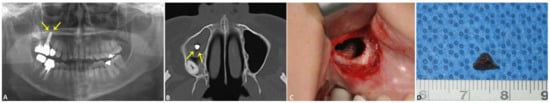

2.1.1. Case 1: Fractured and Damaged Implant-Related Sinusitis Case

2.1.2. Case 2: Fungal Sinusitis with Involved BRONJ Case

2.1.3. Case 3: Apicoectomy of Fixture Case